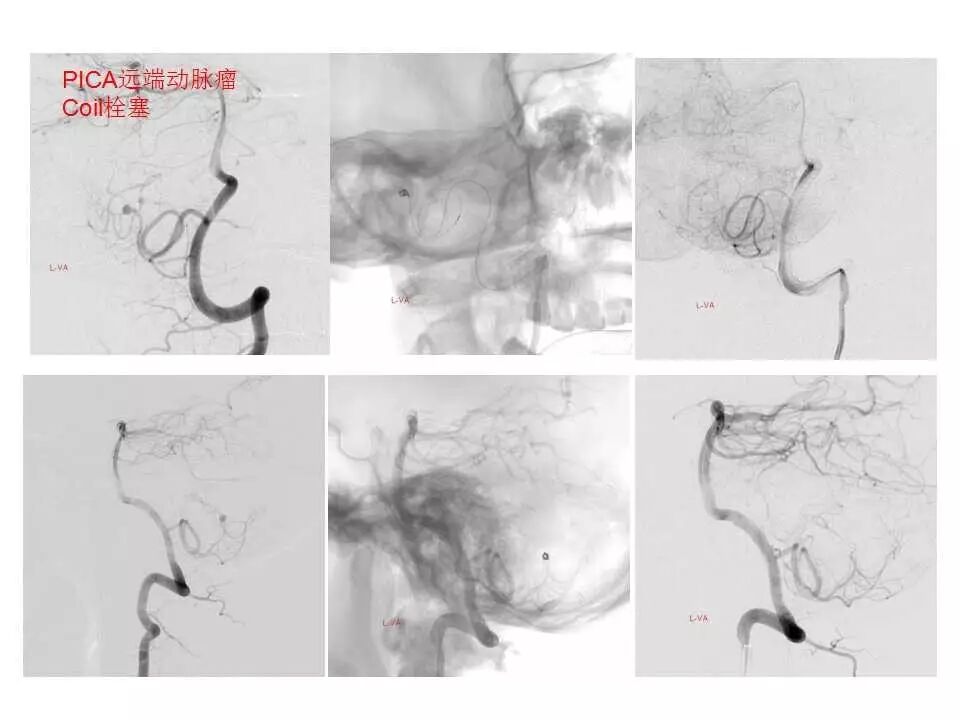

今天为大家分享的是“强生医疗CNV-神经介入专栏”第十五期,由首都医科大学宣武医院何川教授带来的“颅内动脉瘤介入治疗”精彩讲课视频及PPT,欢迎观看、阅读。文章仅代表作者个人观点,如有不同见解,欢迎同道斧正!